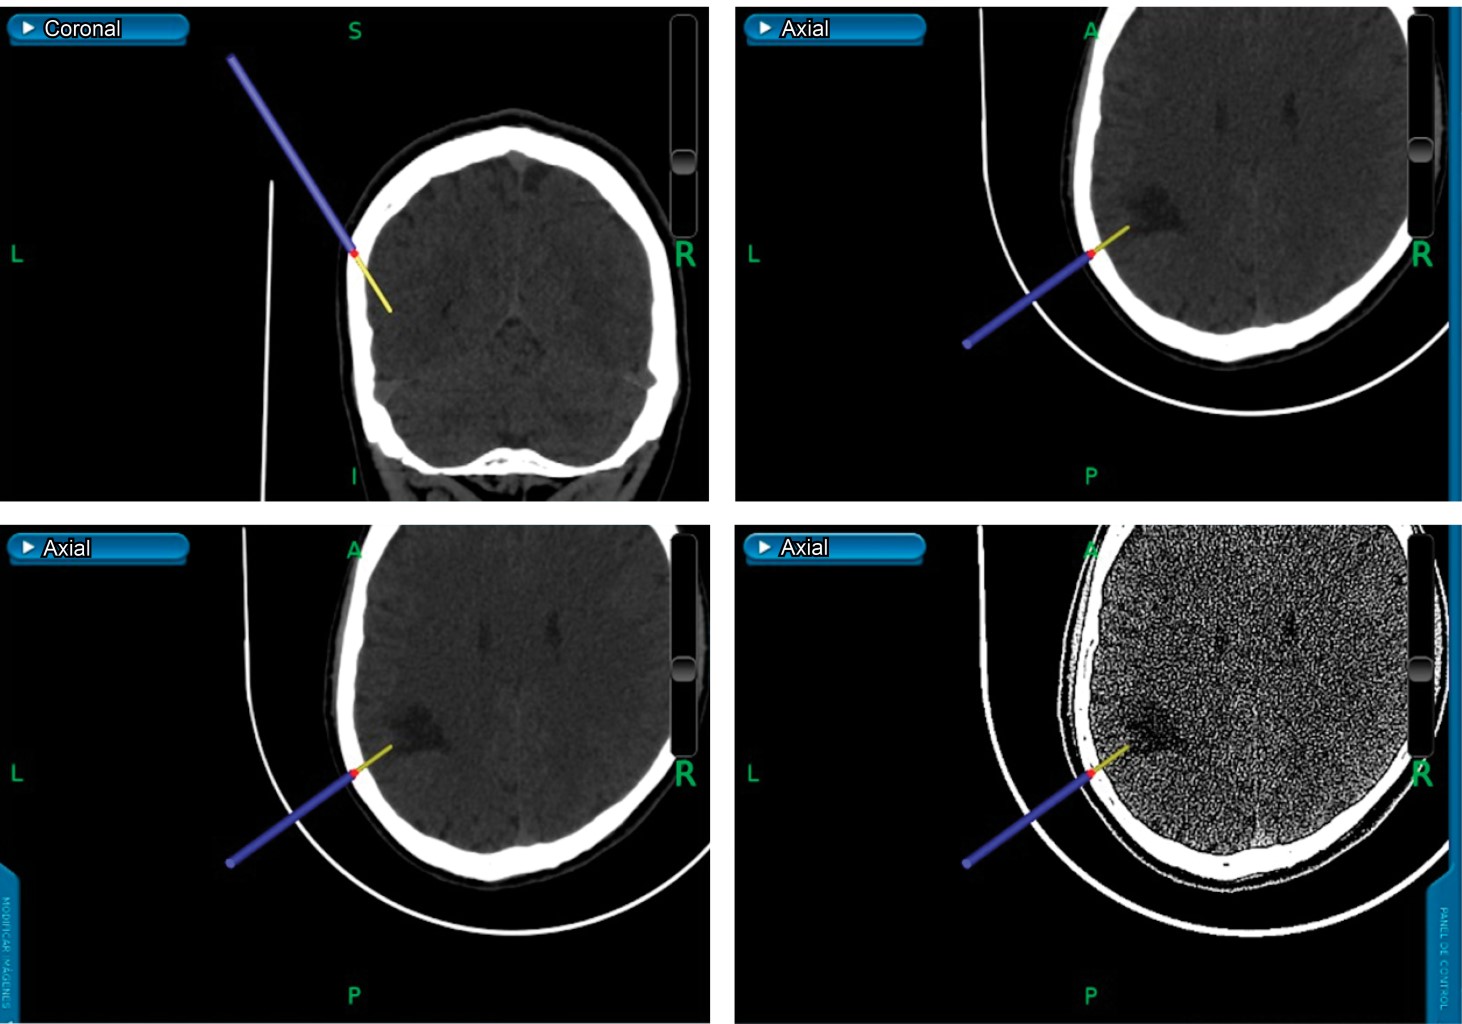

A 41-year-old male patient with a history of traveling to a cave, where he eats raw meat and has poor hygiene conditions. It begins with neurological symptoms, dizziness, dysarthria, difficulty identifying objects, and poor response to medical management. An MRI where a heterogeneous cystic tumor with a mural nodule was found; spectroscopy was performed, showing a lipid peak, suggesting an infectious process. An intervention was performed for stereotaxy, and it was sent to pathology, where they issued us the report of histoplasmosis.

Figure 1